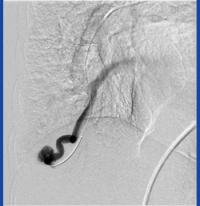

HHT is characterized by internal bleeding due to malformations of blood vessels in organs such as the skin, mucous membranes, lungs, intestines, liver, and brain. Symptoms can range from persistent nosebleeds and lesions to life-threatening complications, such as stroke or heart failure. The condition may require surgical intervention, highlighting the need for accurate screening and coordination of care between all specialists involved. In addition to treatment, the genetic component of HHT emphasizes the importance of genetic counseling to potentially identify other family members who may be at risk.

For patients like Emily Freda, who learned of her family history of HHT just as she herself was diagnosed with an arteriovenous malformation (AVM) in her lung, having the support of a dedicated, knowledgeable medical team is invaluable. "I had never heard of an AVM before and it sounded serious, but nobody in the ER could tell me who to call regarding treatment," said Ms. Freda. "I called the number on the CureHHT.org website the next day, and they put me in touch with Dr. Chheang's office. From my first appointment with her I felt so much calmer about the AVM and the fact that I too have HHT. I can't tell you the peace of mind I have knowing that I have Dr. Chheang on my side."